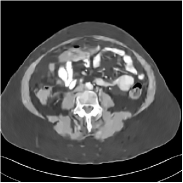

Fig. 3 illustrates the image evolution over SUPER layers (i.e., with evolving network weights in the iterative reconstruction process) for one test case, when using SUPER-WRN-ULTRA. It is apparent that in the early SUPER layers, the proposed SUPER-WRN-ULTRA method mainly removes noise and artifacts, while later SUPER layers mainly reconstruct details such as the bone structures shown in the zoom-in box. A similar behaviour is observed with FBPConvNet-based SUPER methods, which are shown in the supplement (Figs. 13 and 14).

Refer to caption Refer to caption Layer 1RMSE =27.44 HURefer to caption Refer to caption Layer 5RMSE = 26.03 HU

Refer to caption Refer to caption Layer 11RMSE = 25.91HURefer to caption Refer to caption Reference

Figure 3: Image evolution over SUPER layers using the SUPER-WRN-ULTRA method. RMSE values are also indicated.